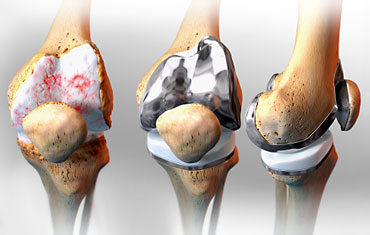

Ендопротезування колінного суглоба

Первинне у пацієнтів з артрозом 3-4 стадії, що супроводжується деформаціями (викривленням) колінного суглоба і контрактурами (порушенням згинання та розгинання). Середній термін перебування пацієнта в клініці 3-4 дня.

Ревізійне (заміна компонентів зношеного протеза, періпротезние переломи, нестабільність компонентів протеза і т.д). Термін перебування в клініці визначається індивідуально.